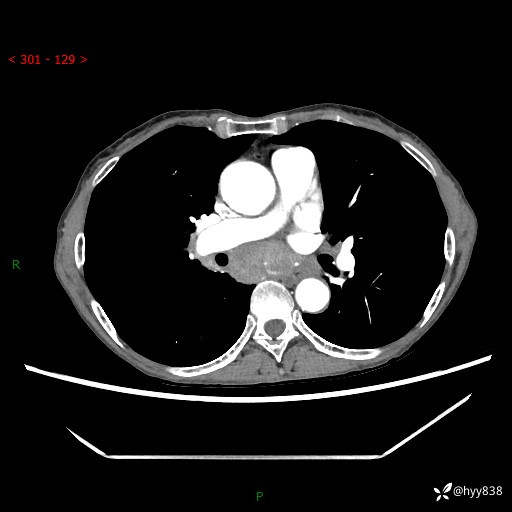

【患者信息】:69岁/女

【主诉】:发现肺占位3天余

【现病史及既往史】:患者3天余前因既往肺气肿复查胸部CT发现“右肺下叶结节、双肺多发结节、双肺门及纵膈淋巴结增大”,平素偶有咳白色粘液痰,下肢乏力,无明显低热、盗汗、咯血、胸痛、喘气等不适,今为求明显结节性质遂来我院门诊就诊,门诊以“孤立性肺结节”收治入院。 起病以来,患者精神饮食睡眠一般,大小便正常,体力无明细变化,体重近年来较前下降。

【检查】:胸部CT增强